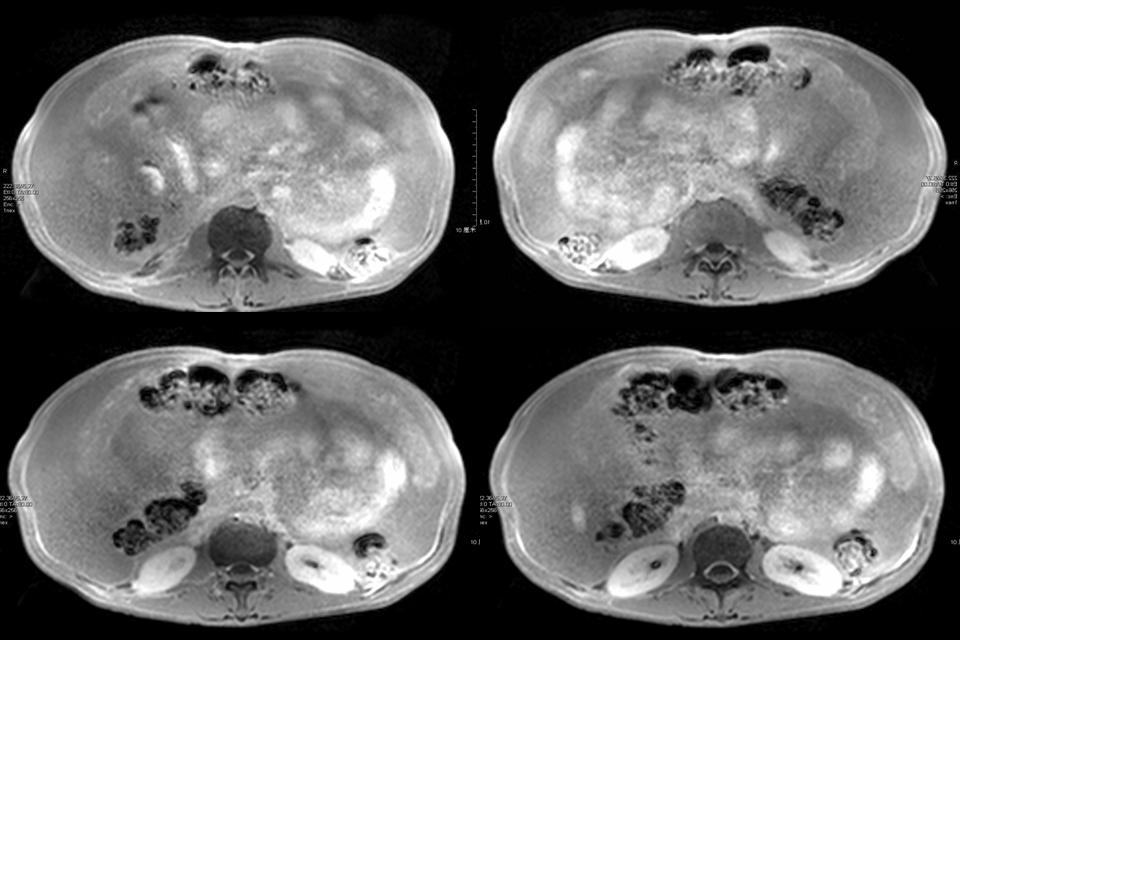

男性,47岁,乙肝病史十余年,无发热、腹痛,无恶性、呕吐,无下肢浮肿,否认结核病史,尘肺史 实验室检查:肝肾功能正常,afp、cea(—),腹水生化:黄色浊,李凡他实验(++++),间皮细胞85%,中性粒细胞5%,淋巴细胞10%;

大量腹水、脾门占位(长t1短t2为主混杂信号)------考虑为恶性肿瘤伴腹膜转移、腹水合并感染。

腹水很多,抽腹水检查发现间皮细胞增多

考虑为恶性肿瘤伴腹膜转移、腹水合并感染。